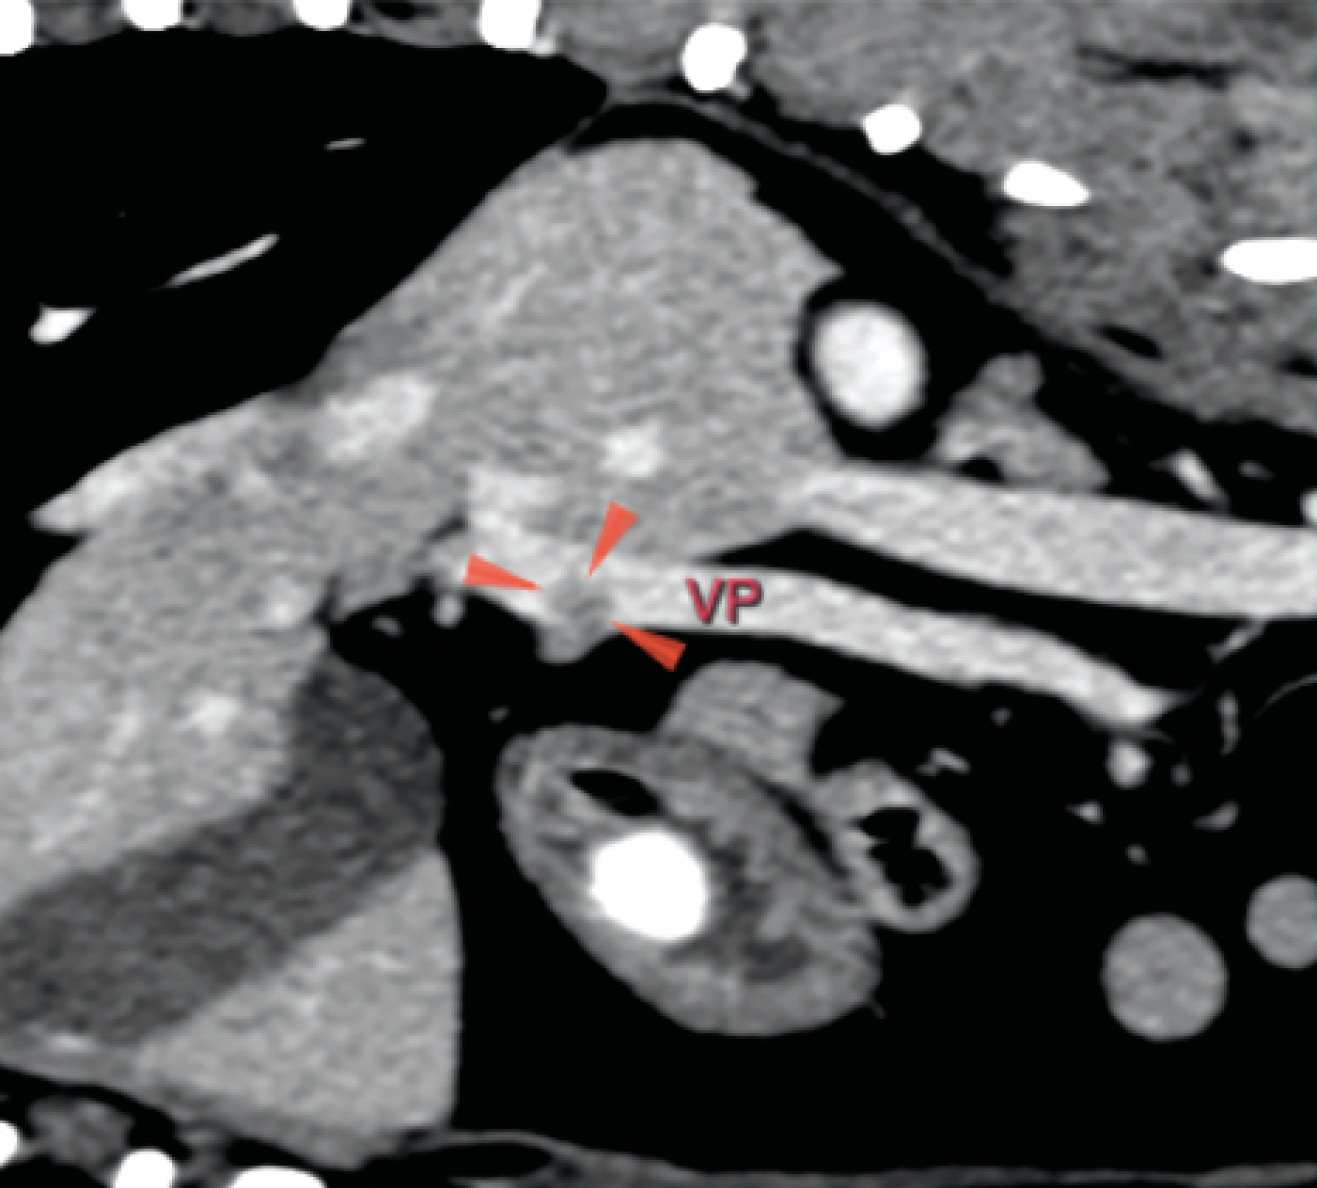

La ecografía abdominal reveló una lesión en el parénquima del cuerpo pancreático con posible invasión vascular a la vena porta. Una TC abdominal con contraste evidenció la lesión asociada al cuerpo del páncreas, con invasión de la vena porta (imágenes 1A y 1B), junto con la presencia incidental de un cuerpo extraño gástrico y signos de enfermedad degenerativa torácica y lumbosacra. Se realizó la extracción endoscópica del cuerpo extraño mediante gastroscopia durante el procedimiento anestésico.

Se realizó una laparotomía exploratoria por línea media ventral y se observó un nódulo en el cuerpo del páncreas con invasión de un trombo tumoral en la vena porta y otro nódulo de menor tamaño en el lóbulo izquierdo (imágenes 2A y 2B).

Actualmente, la TC se considera la técnica de referencia para la detección y localización preoperatoria de insulinomas y metástasis. La ecografía resultaría útil si se consideran apropiados los aspirados o biopsias por aspiración con aguja fina ecoguiados de cualquier lesión hepática, ganglios linfáticos regionales y ganglios linfáticos agrandados detectados en la CT para facilitar la estadificación precisa de la TNM preoperatoria.

En nuestro caso, la ecografía abdominal identificó una lesión en el parénquima del cuerpo pancreático con posible invasión vascular y nódulos linfáticos aumentados de tamaño (aunque no metastásicos); estos hallazgos se confirmaron en la TC. Sin embargo, la enfermedad metastásica se evaluó mediante la inspección macroscópica del hígado y la localización de un segundo nódulo en el lóbulo pancreático izquierdo, que fue reseccionado.